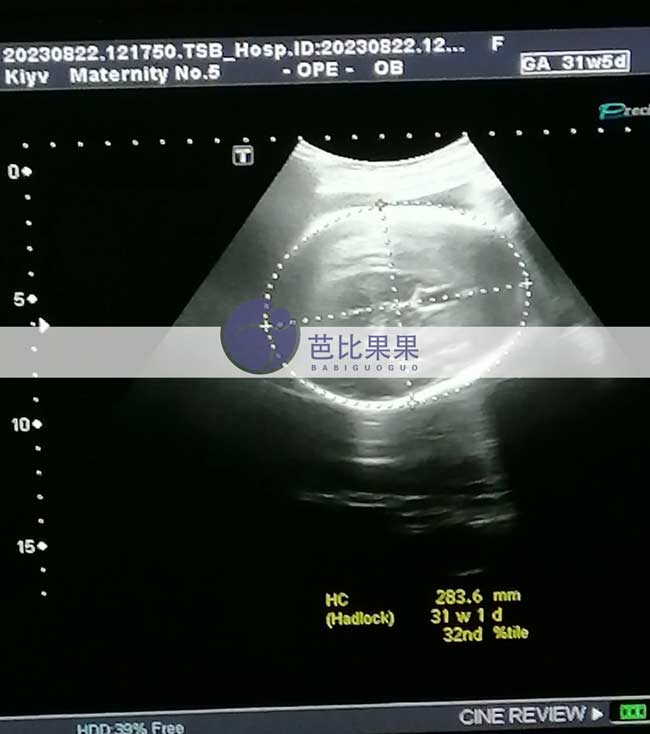

Z先生家的乌克兰试管妈妈按时来做了孕31周+的B超,胎儿已经越来越大了,期待TA的到来